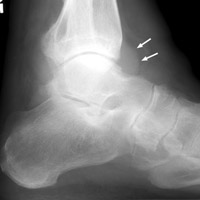

One normal ankle radiograph (A), and one abnormal ankle radiograph (B) revealing a moderate effusion. The teardrop shaped density seen extending anteriorly from the ankle joint along the neck of the talus has been referred to as the "teardrop sign" of ankle effusion. This is a useful sign in the diagnosis of ankle joint effusion, and may alert the diagnostician to possible underlying pathology.

Lateral normal ankle - Click on the image for a larger versionALateral ankle - Click on the image for a larger versionB